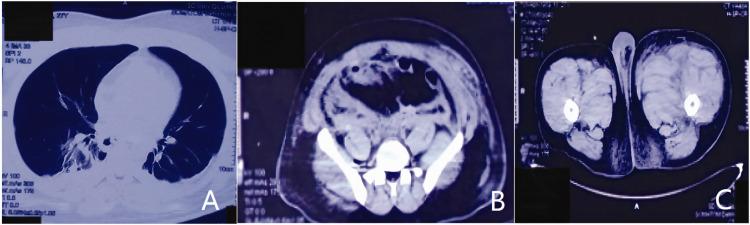

Acquired haemophilia A (AHA) is a rare haemorrhagic disease characterized by spontaneous extensive subcutaneous haemorrhage and soft tissue haematoma. The activated partial thromboplastin time is significantly prolonged and cannot be corrected by normal plasma. Approximately 50% of AHA patients lack a specific aetiology, so this can easily result in a misdiagnosis. This current case report describes a 27-year-old male that presented with gingival bleeding, haematuria and haematochezia with no obvious cause. At first, it was thought that he might have experienced anticoagulant rodenticide poisoning, but the subsequent anticoagulant rodenticide test was negative. At the same time, the patient was screened for mutations associated with bleeding and coagulation diseases. Two mutations were identified: a p.Y471H mutation the plasminogen activator, tissue type () gene; and a p.Y244Y mutation the serpin family E member 1 () gene. It should be noted that patient had no previous history of thrombosis or haemorrhagic disease, which confused the diagnosis. A professional haemophilia research centre provided clarification of the diagnosis when anti-factor VIII antibodies were detected. The patient was treated with 30 mg/day prednisone orally. Multiple follow-up examinations showed continuous complete remission. No factor VIII antibodies were detected in his blood and coagulation factor VIII increased significantly.

获得性血友病 A (AHA) 是一种罕见的出血性疾病,其特征为自发性广泛皮下出血和软组织血肿。活化部分凝血活酶时间显著延长,且不能被正常血浆纠正。约 50%的 AHA 患者缺乏特定病因,因此容易导致误诊。本病例报告描述了一名 27 岁男性,因牙龈出血、血尿和血便就诊,无明显病因。起初,考虑可能是抗凝剂中毒,但随后的抗凝剂检测为阴性。同时,对患者进行了与出血和凝血疾病相关的基因突变筛查。发现了两个突变:纤溶酶原激活物,组织型(p.Y471H)基因和丝氨酸蛋白酶抑制剂家族 E 成员 1(p.Y244Y)基因。值得注意的是,患者无既往血栓或出血性疾病史,这增加了诊断的难度。当检测到抗因子 VIII 抗体时,专业的血友病研究中心明确了诊断。给予患者 30mg/天泼尼松口服治疗。多次随访检查显示持续完全缓解。患者血液中未检测到因子 VIII 抗体,凝血因子 VIII 显著增加。